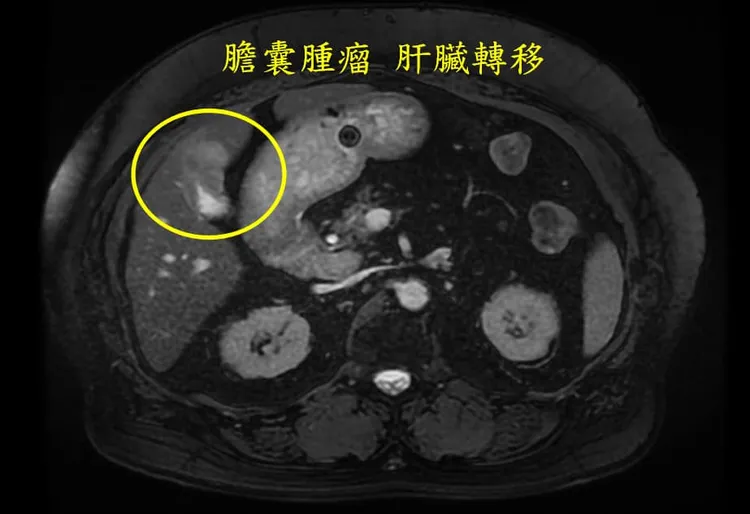

醫師林相宏在粉專「胰臟醫師 林相宏 禾馨民權內科診所」提到,一名65歲女性平時沒有什麼不舒服,頂多右上腹部 有時會感到一點疼痛,不過因為不是常發生,她也沒有特別注意,這次因為上吐下瀉太厲害去掛急診,「急診斷層掃描一掃不得了了,赫然發現膽囊有腫瘤,而且更不幸的是淋巴、肝臟、腹膜都已經轉移,到現在家屬和病患還是不敢置信!」

林相宏表示,膽囊癌早期症狀並不明顯,大部分被誤以為「膽結石」或「慢性膽囊炎」治療,但是出現食慾不振、噁心、持續右上腹痛、體重下降、黃疸、腹部腫塊等症狀要注意,建議有上訴狀況者定期接受腹部超音波檢查,方便、快速評估膽囊結石、發炎狀況。